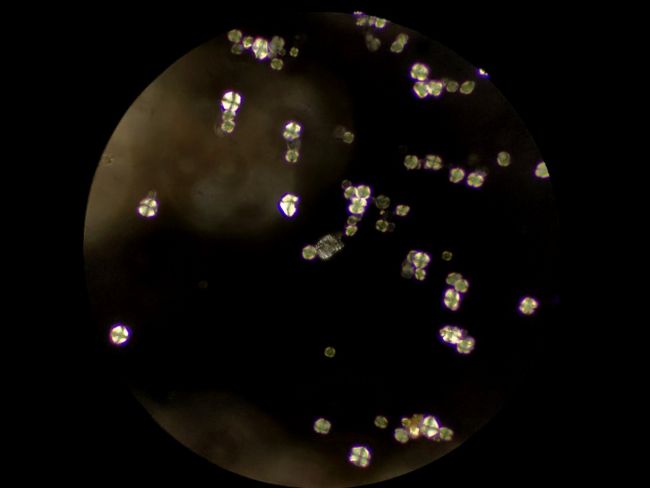

偏光下的中藥顆粒

偏光觀察是對結晶物質的形態進行觀察和測量的一種技術,在生物顯微鏡ML31基礎上加入偏光附件,即可升級為簡易偏光顯微鏡ML31-P,正交偏光下可以看到顆粒出現了偏光反應,形成以粒心為中心的黑色“十”字外觀,這是淀粉粒的典型特征。

在其他視野中,我們也看到了一些其他偏光反應,可能是草酸鈣簇晶之類成分,也可能是玻片或者水中的雜質。